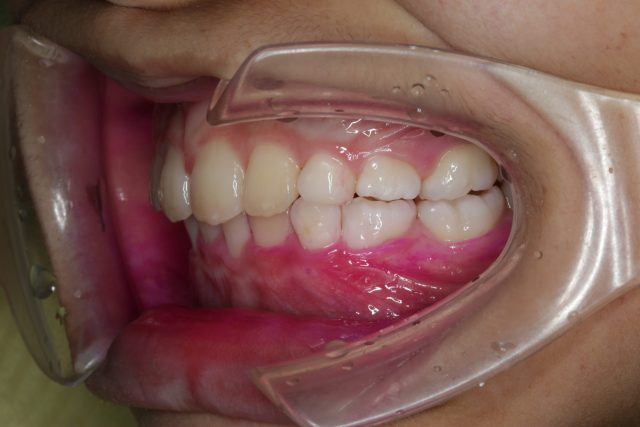

8歳男の子インビザラインファースト:永久歯スペース不足を解消

| 年齢・性別・主訴 | 8歳男の子 永久歯が並ぶスペースが足りない |

他のAfter